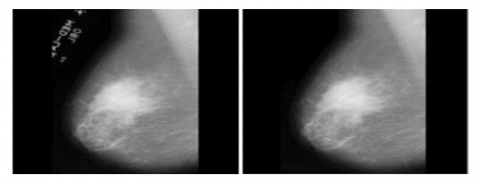

3.1.1 Noise removal

Mammograms can be affected by variety of noises, such as gaussian, speckle, salt-and-pepper noise. This noise may diminish the efficacy of classification methods. Using a 2D median filter may efficiently eliminate noise while retaining crucial information for categorization. Figure 3 displays the picture after the implementation of a 2D median filter.

Figure 3. Normal vs noise removed image